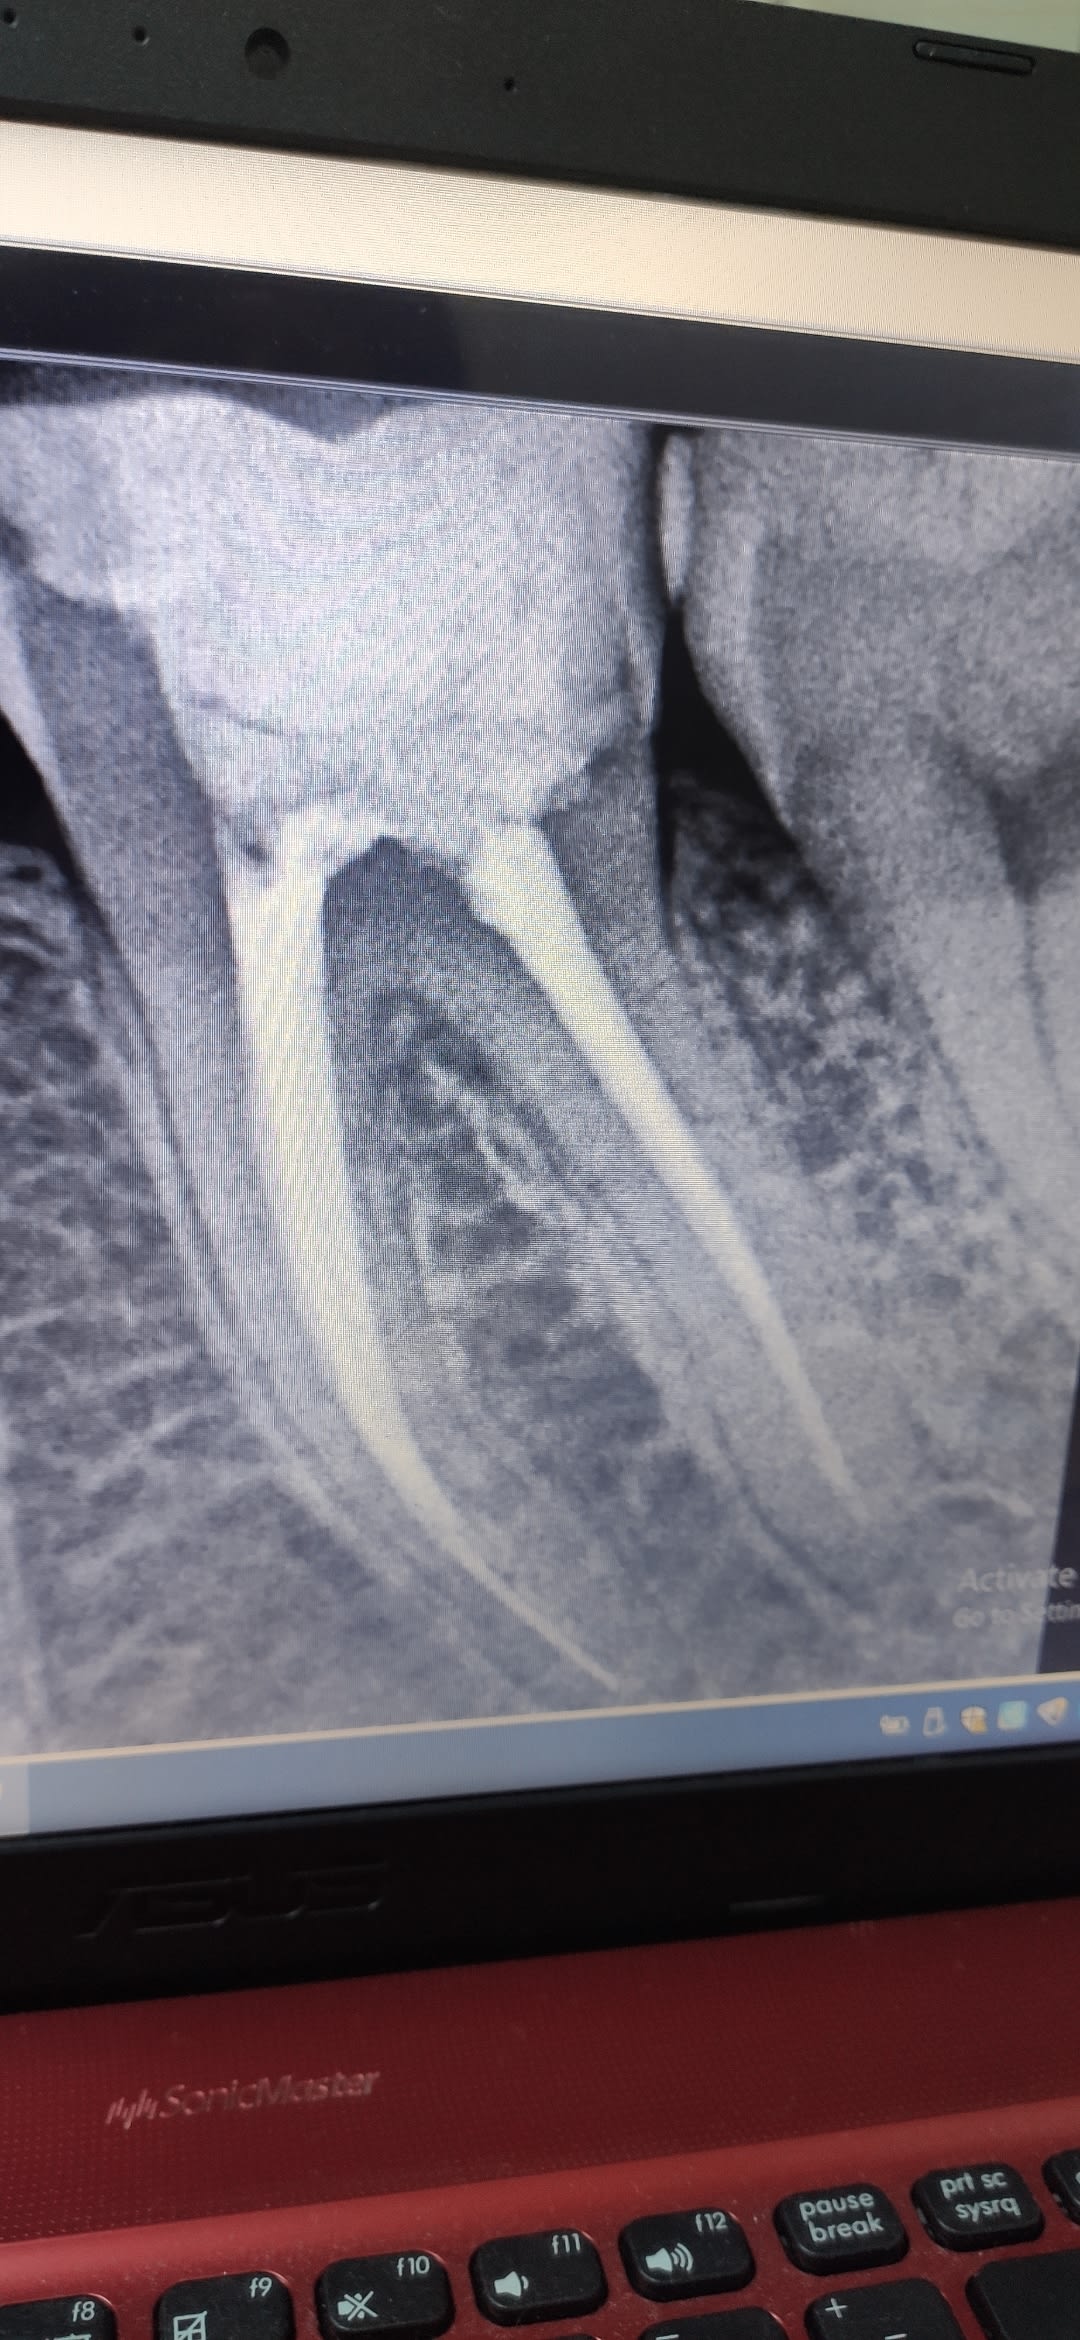

Resultat de mon endo

Lime endomoteur casse MV :s

Et finalement en distal c'était surement de l'hydroxyde de calcium car ça a plus ou moins disparu !!

(2seances d'hydroxyde de calcium, chaque seance irrigation Hypo, toujours sous digue, d'où la décision de laisser la Lime en place, la patiente est informée et rassurée)